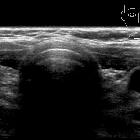

fehlende Schilddrüse in orthotoper Lage

Ectopic

thyroid tissue presenting as a midline neck mass with absent orthotopic thyroid gland. Axial ultrasound section at level just below cricoid cartilage does not show evidence of any normal thyroid tissue at an orthotopic location.